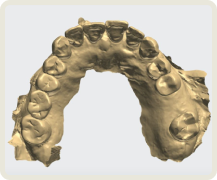

치아 제작시 국내 최고 수준의 장비를 보유한

디지털 치과 전문 기공소와 협업합니다.

implant

Oral Scanner

모든 과정은 이로운치과의 의료진과 디지털 치과기공 전문인 와이앤씨 기공소 와의 긴밀한 커뮤니케이션 하에 협업하여 진행합니다.